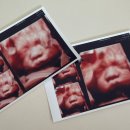

서울의원에서 검사한 초음파 CD와 세침결과병리결과지, 세침슬라이드, 진료의뢰서, 4시간 금식 세침검사 슬라이드를 받기 위해 다시 땡큐로 가서 슬라이드 원본을 받아왔다. 슬라이드 원본은 판독하는데 2주 정도 소요되고, 꼭 3개월? 안에 찾아가야 한다. 그렇지 않으면,, 폐기된다고 한다. 나는 신촌 세브란스...